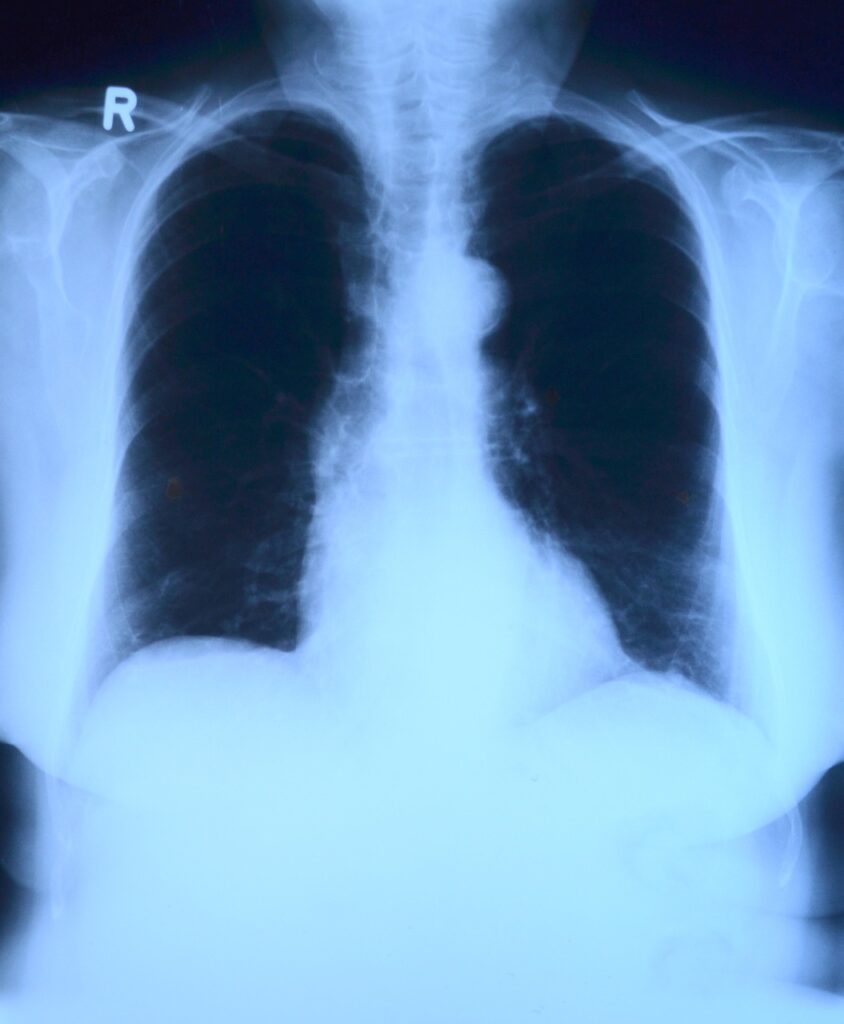

„Svi naši sugrađani, stariji od 50 godina, koji imaju pušački staž duži od 30 godina, su ciljana populacija, odnosno ključne osobe za ovaj skrining. Njima će biti urađen CT pregled za skrining karcinoma pluća, koji se radi po niskodoznom protokolu“, naveo je ministar. Rekao je i da na svaka dva sata jedna osoba premine od raka pluća.